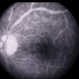

- Behcet's Disease, Behcet's uveitis, FA late phase leakage

- DEEPAK BHOJWANI, RAGHUDEEP EYE HOSPITAL, AHMEDABAD.

- A 19-year-old boy presented with with recurrent oral and genital ulcers along with blurring of vision. Systemically he was HLA B-51 Positive suggesting Behcet's Disease. The FFA photograph depicts the classic small vessel immune mediated vasculitis predominantly affecting the capillaries (capillaropathy).